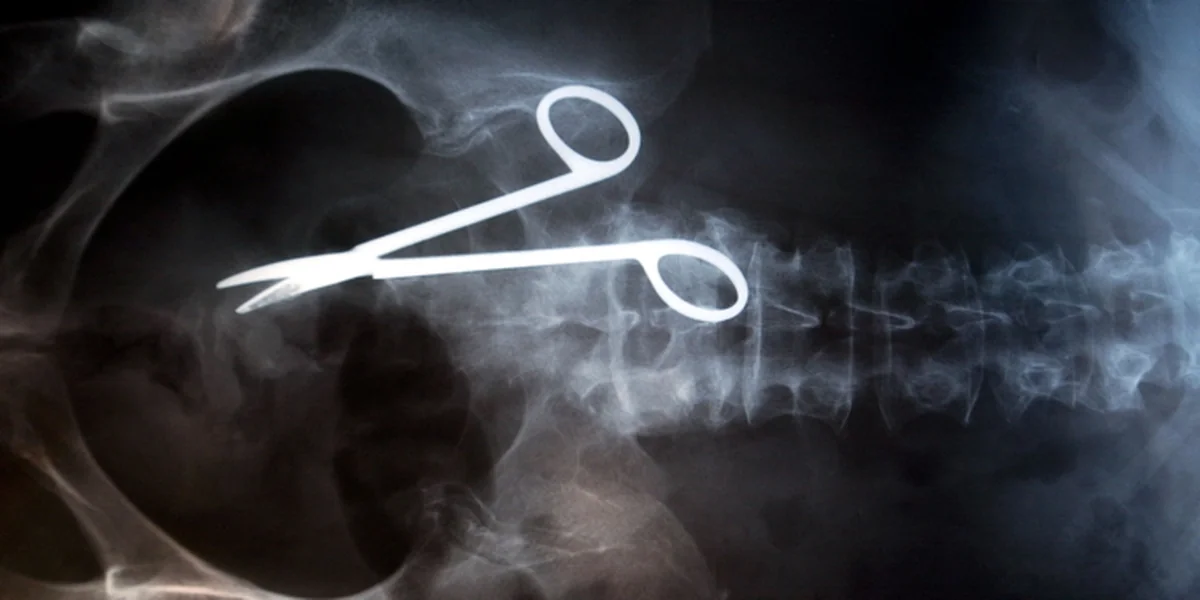

Frage der Beweislast: Hier dürfte der Fall klar sein. Bild: ap

Nach wie vor müssten Betroffene – außer bei offensichtlichen Fehlern wie falsch amputierten Gliedmaßen – beweisen, dass der Arzt einen Fehler gemacht hat. Das könnten sie aber nicht, weil ihnen das Fachwissen fehle. Verbraucherschützer, Gesundheitsexperten und die Opposition im Bundestag fordern daher: Der Arzt soll beweisen, dass er keinen Fehler gemacht hat. Das indes lehnt die Bundesregierung ab.